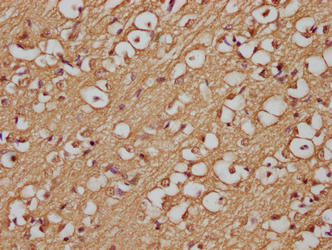

Immunohistochemistry of paraffin-embedded human brain tissue using CSB-MA0019501A0m at dilution of 1:200